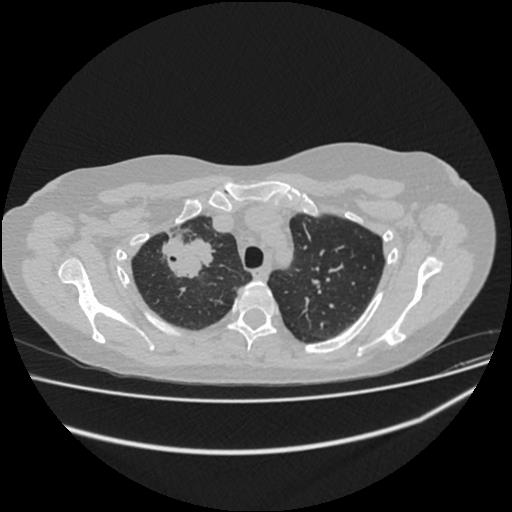

Рак легкого